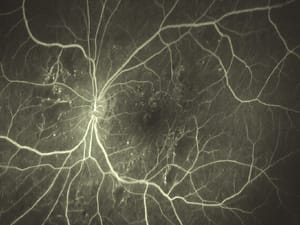

This Optomap images shows a normal fluorescein angiography.

Optomap fluorescein angiogram showing extensive leakage near the optic disc. |